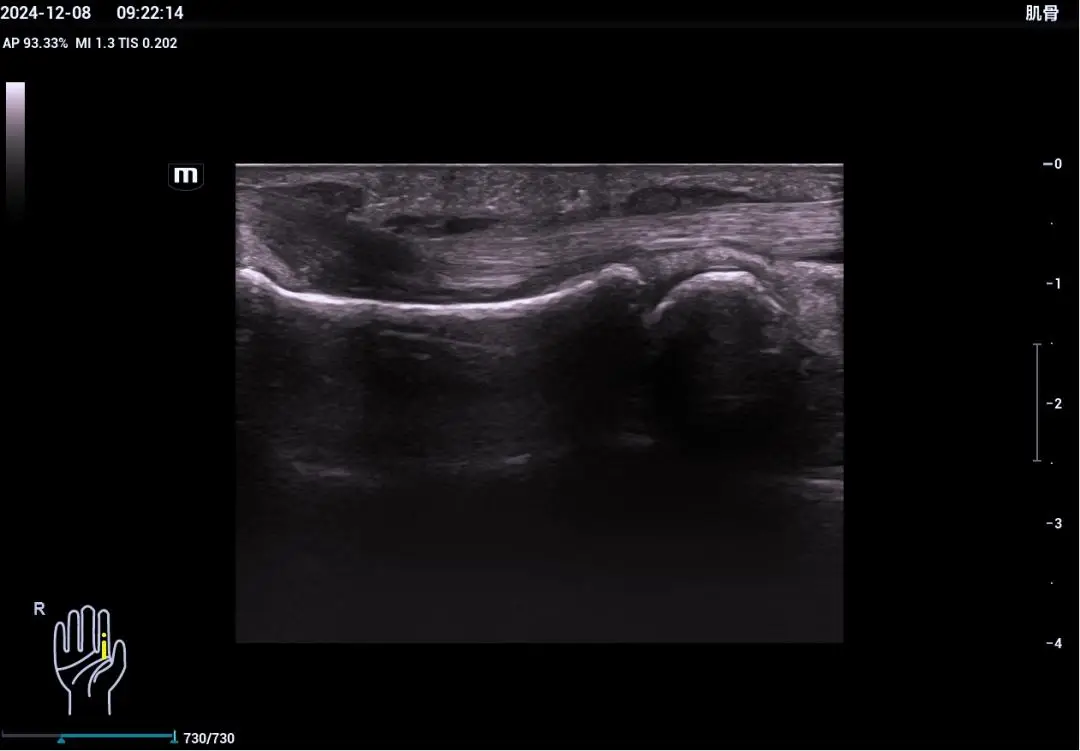

关于肌骨超声的介绍 |

大家好, 今天我给大家介绍一下什么是肌骨超声,他是利用专用高频探头来诊断肌肉骨骼疾病的一种新兴的超声检查方法,那么肌骨超声有哪些优势: 一、肌骨超声相比传统的检查方法,如X线、CT、核磁共振具有无创、无辐射、无禁忌廉价等诸多优势之外,还具有能够对肌肉、肌腱的运动进行实时动态观察的独特优势,尤其是高频超声探头的应用,细微分辨率的显著提高,能够清晰的显示肌肉、肌腱、韧带和神经组织病变,如:炎症、肿瘤、损伤和畸形引起的结构异常,还可以进行介入性操作引导,达到可视化操作提高穿刺成功和疗效的目的。

二、肌骨超声可以诊断哪些疾病呢? 1、外伤运动所致的关节和周围肌肉、肌腱以及韧带的损伤。 2、免疫凤湿性疾病 3、四肢软组织肿瘤性病变 4、部分骨肿瘤病变 5、骨肿瘤术后评估手术区情况 6、神经病变 我们肌骨超声在临床应用方面还可以与骨科、康复科、疼痛科、内分泌科、风湿科开展多学科临床及科研协作。